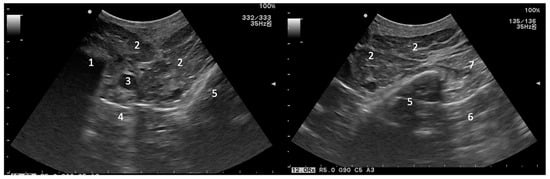

2.2. Ultrasound